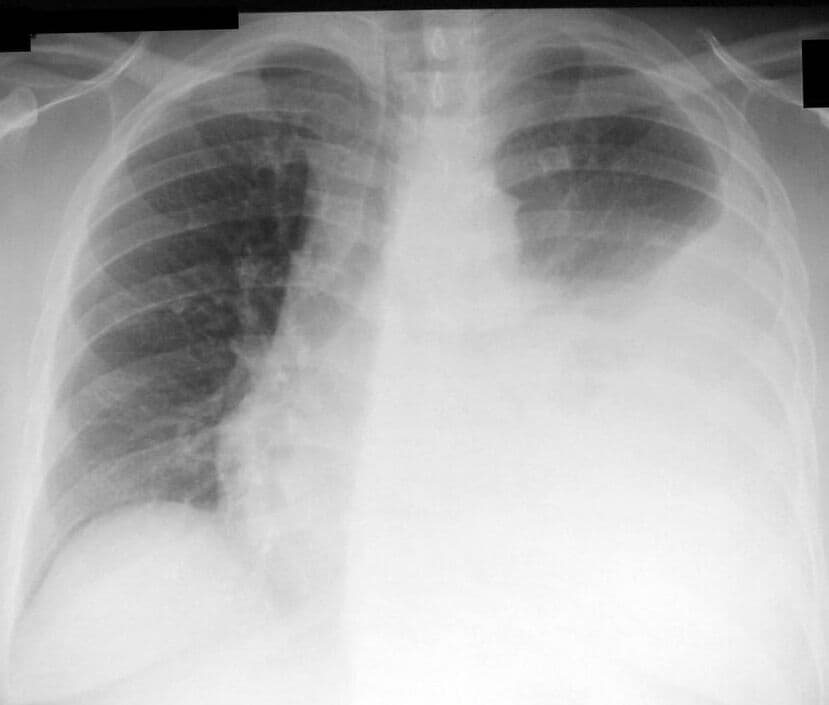

Thoracentesis ˌθɔːrəsᵻnˈtiːsᵻs, also known as thoracocentesis (from Greek θώραξ thōrax 'chest, thorax'—GEN thōrakos—and κέντησις kentēsis 'pricking, puncture'), pleural tap, needle thoracostomy, or needle decompression (often used term), is an invasive medical procedure to remove fluid or air from the pleural space for diagnostic or therapeutic purposes. A cannula, or hollow needle, is carefully introduced into the thorax, generally after administration of local anesthesia. The procedure was first performed by Morrill Wyman in 1850 and then described by Henry Ingersoll Bowditch in 1852. The recommended location varies depending upon the source. Some sources recommend the midaxillary line, in the eighth, ninth, or tenth intercostal space. Whenever possible, the procedure should be performed under ultrasound guidance, which has shown to reduce complications. Tension pneumothorax is a medical emergency that requires needle decompression before a chest tube is placed. This procedure is indicated when unexplained fluid accumulates in the chest cavity outside the lung. In more than 90% of cases analysis of pleural fluid yields clinically useful information. If a large amount of fluid is present, then this procedure can also be used therapeutically to remove that fluid and improve patient comfort and lung function. The most common causes of pleural effusions are cancer, congestive heart failure, pneumonia, and recent surgery. In countries where tuberculosis is common, this is also a common cause of pleural effusions. When cardiopulmonary status is compromised (i.e. when the fluid or air has its repercussions on the function of heart and lungs), due to air (significant pneumothorax), fluid (pleural fluid) or blood (hemothorax) outside the lung, then this procedure is usually replaced with tube thoracostomy, the placement of a large tube in the pleural space. An uncooperative patient or a coagulation disorder that cannot be corrected are relative contraindications.